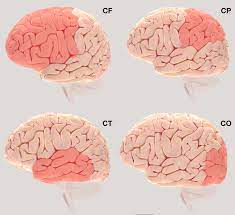

Las causas de éste trastorno no están del todo claras, aunque se considera que son factores genéticos los que «programan» un desarrollo diferente del cerebro. Hipometabolismo en frontal, cerebro social La falta de apoyos específicos para las personas con síndrome de asperger dificulta su trayectoria educativa y el acceso al mercado laboral en igualdad de condiciones. Asperger syndrome (as), also known as asperger's, is a neurodevelopmental disorder characterized by significant difficulties in social interaction and nonverbal communication. Síndrome o trastorno de asperger.